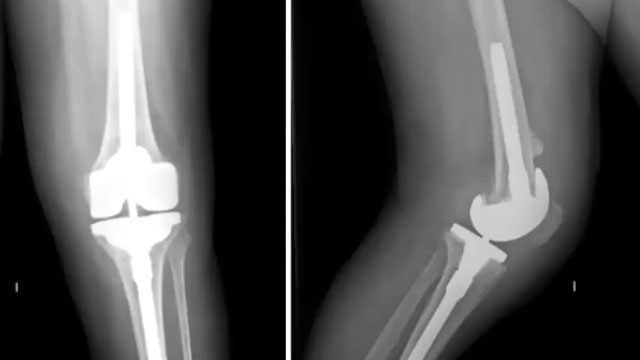

Revision knee replacement surgery for addressing complications or failure of a previous implant

Revision knee replacement surgery is a critical procedure designed to address complications or failures arising from a previous knee replacement. As patients age or as their needs change, it may become necessary to replace or adjust an existing implant to restore functionality and alleviate pain. This surgery can significantly enhance quality of life and mobility for individuals experiencing issues with their current knee replacement.

- Implant Placement: A new prosthesis is then implanted, tailored to the patient’s specific anatomy and needs, ensuring optimal alignment and stability.